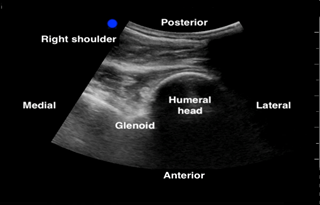

In the shoulder POCUS, a posterior approach allows the visualization of the humeral head in relation to the glenoid fossa. The following are the steps to perform in order to obtain this view.

- The scapular spine can be identified as a hyperechoic line with a posterior shadow. Note that the deltoid and the infraspinatus muscles can be seen above the scapular spine (See Figure 1).

- Continue sliding the probe laterally along the scapular spine towards the glenohumeral joint (GHJ), until visualizing the glenoid fossa which is closely followed by the humeral head (See Figure 1). Positioning the glenoid fossa and the GHJ in the center of the screen while adjusting the depth, will result in a better image quality. Asking the patient to externally and internally rotate the affected shoulder will aid in identifying the humeral head (See Figure 2).

Figure 1: Normal right shoulder